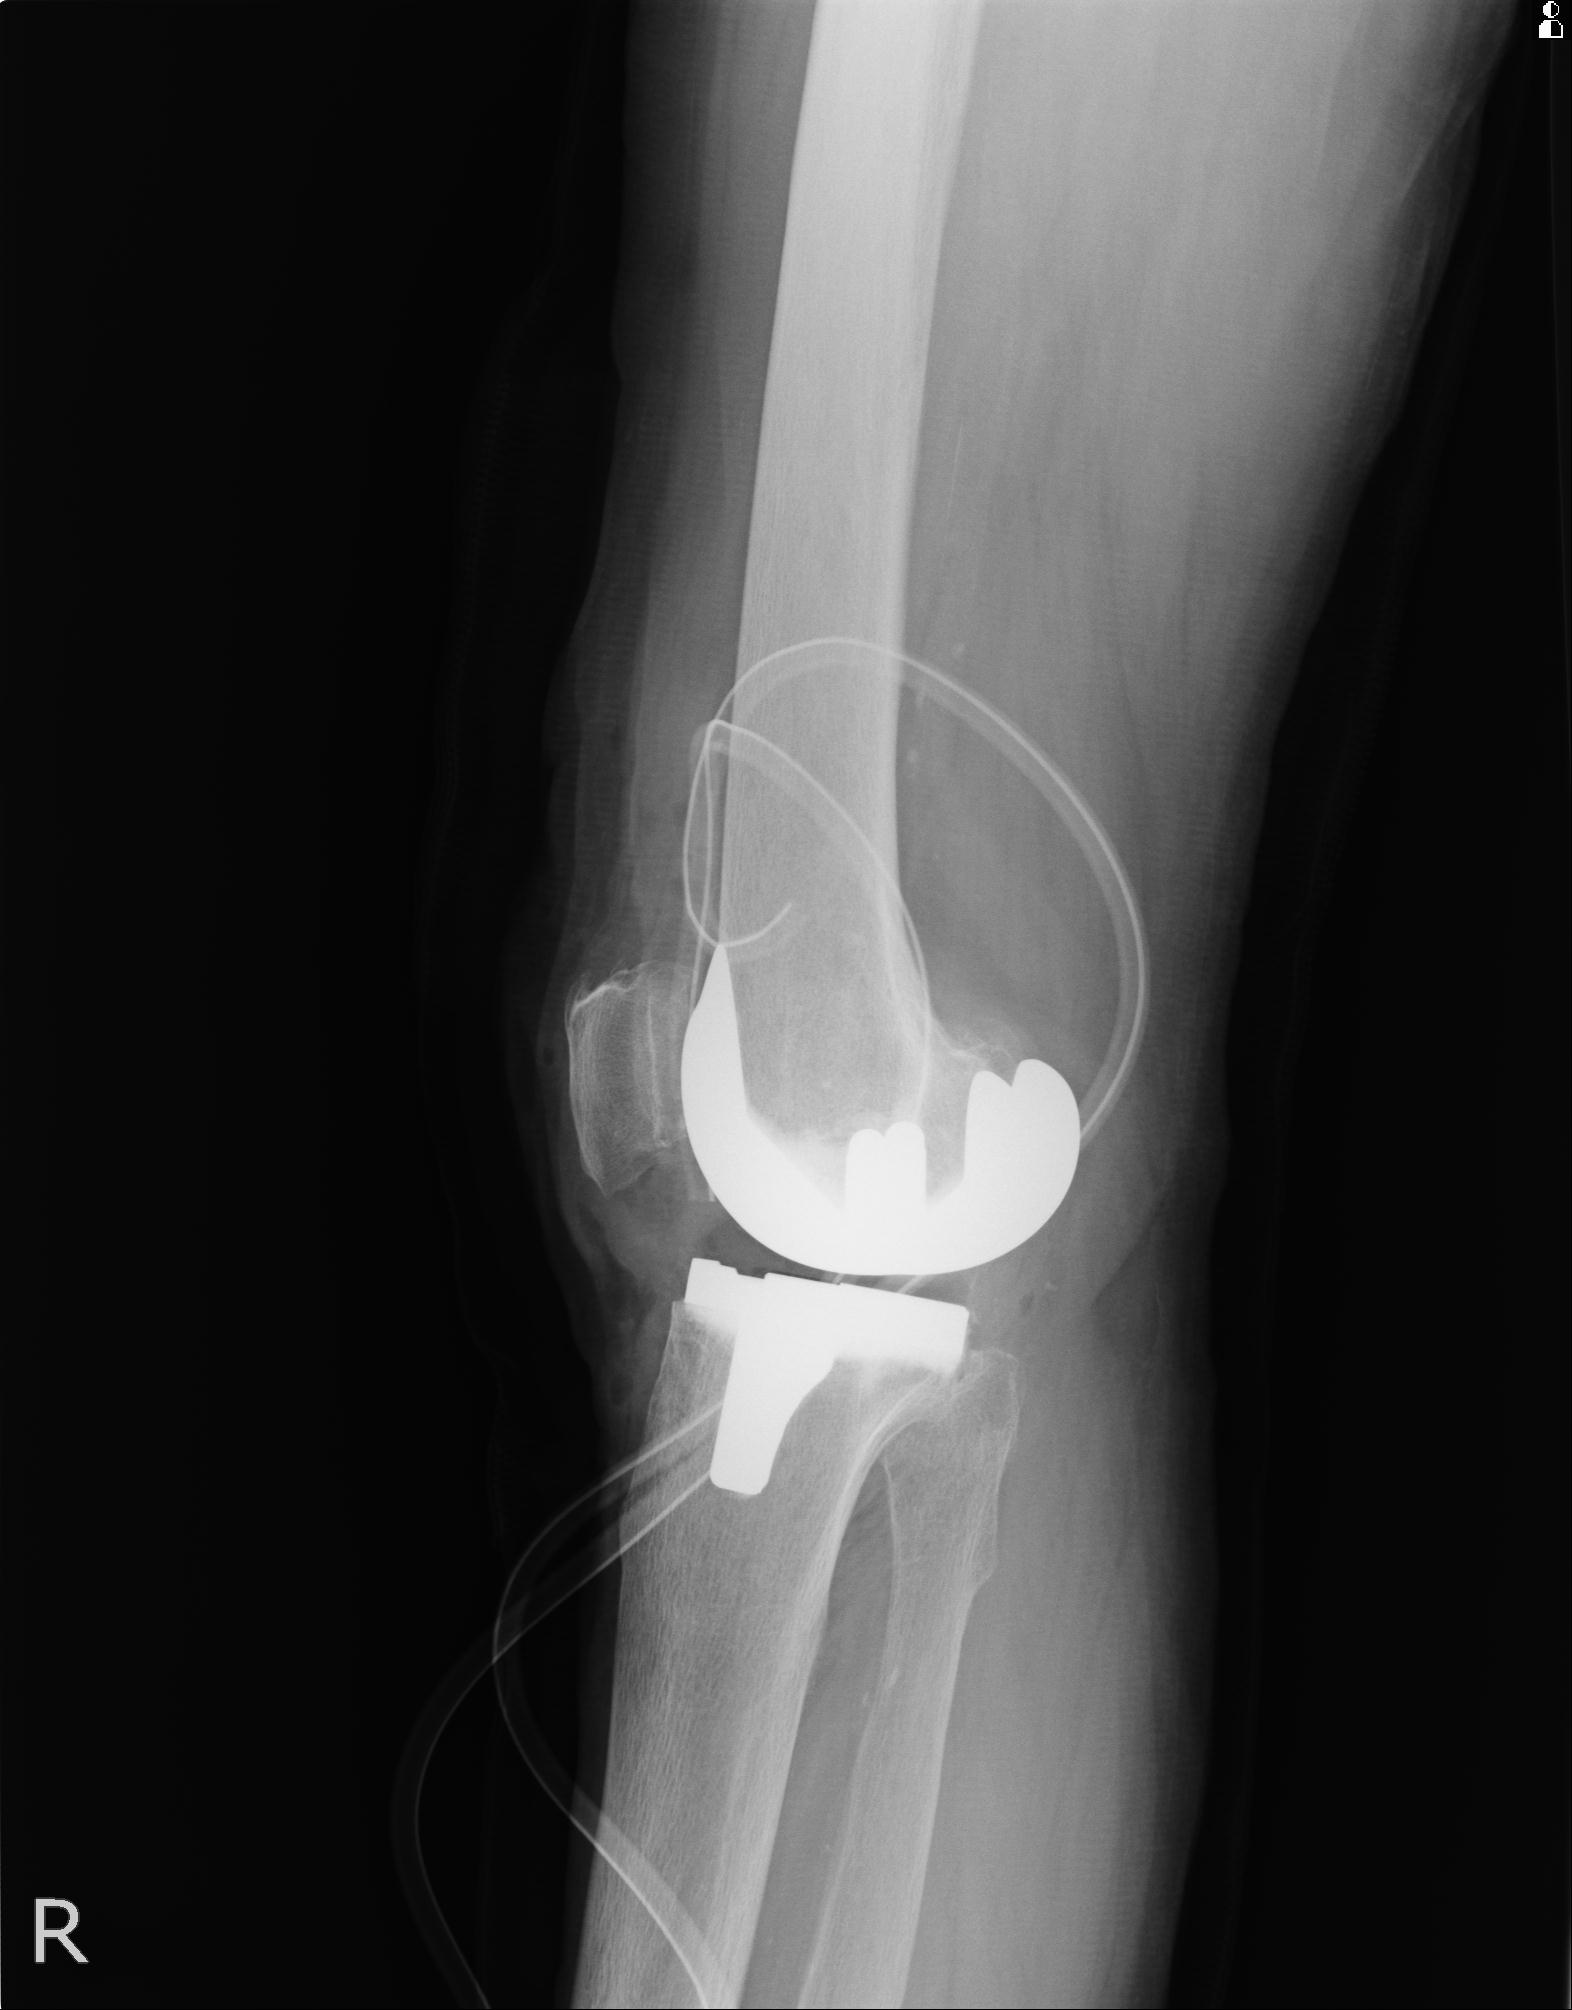

100612 11/25 1/20 右膝 2R 84歳女性 右TKA